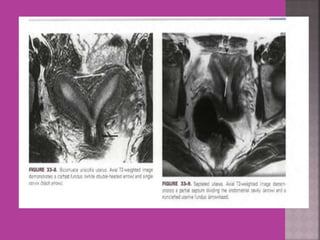

UTERUS ----DIDELPHYS

 Study ofnormal uterus and adnexa – with aim to have clear image of normal myometrium, endometrium , ovary and follicles within the ovary.  Myoma—to differentiate myoma from adenomyoma.localization of myoma—sub serous/ intra mural or sub mucous.  Adenomyosis---accurate diagnosis.  Congenital uterovaginal anomalies— bicornuate, septate,subseptate , unicornuate, didelphys ,rudimentary horn and vaginal atrasia etc